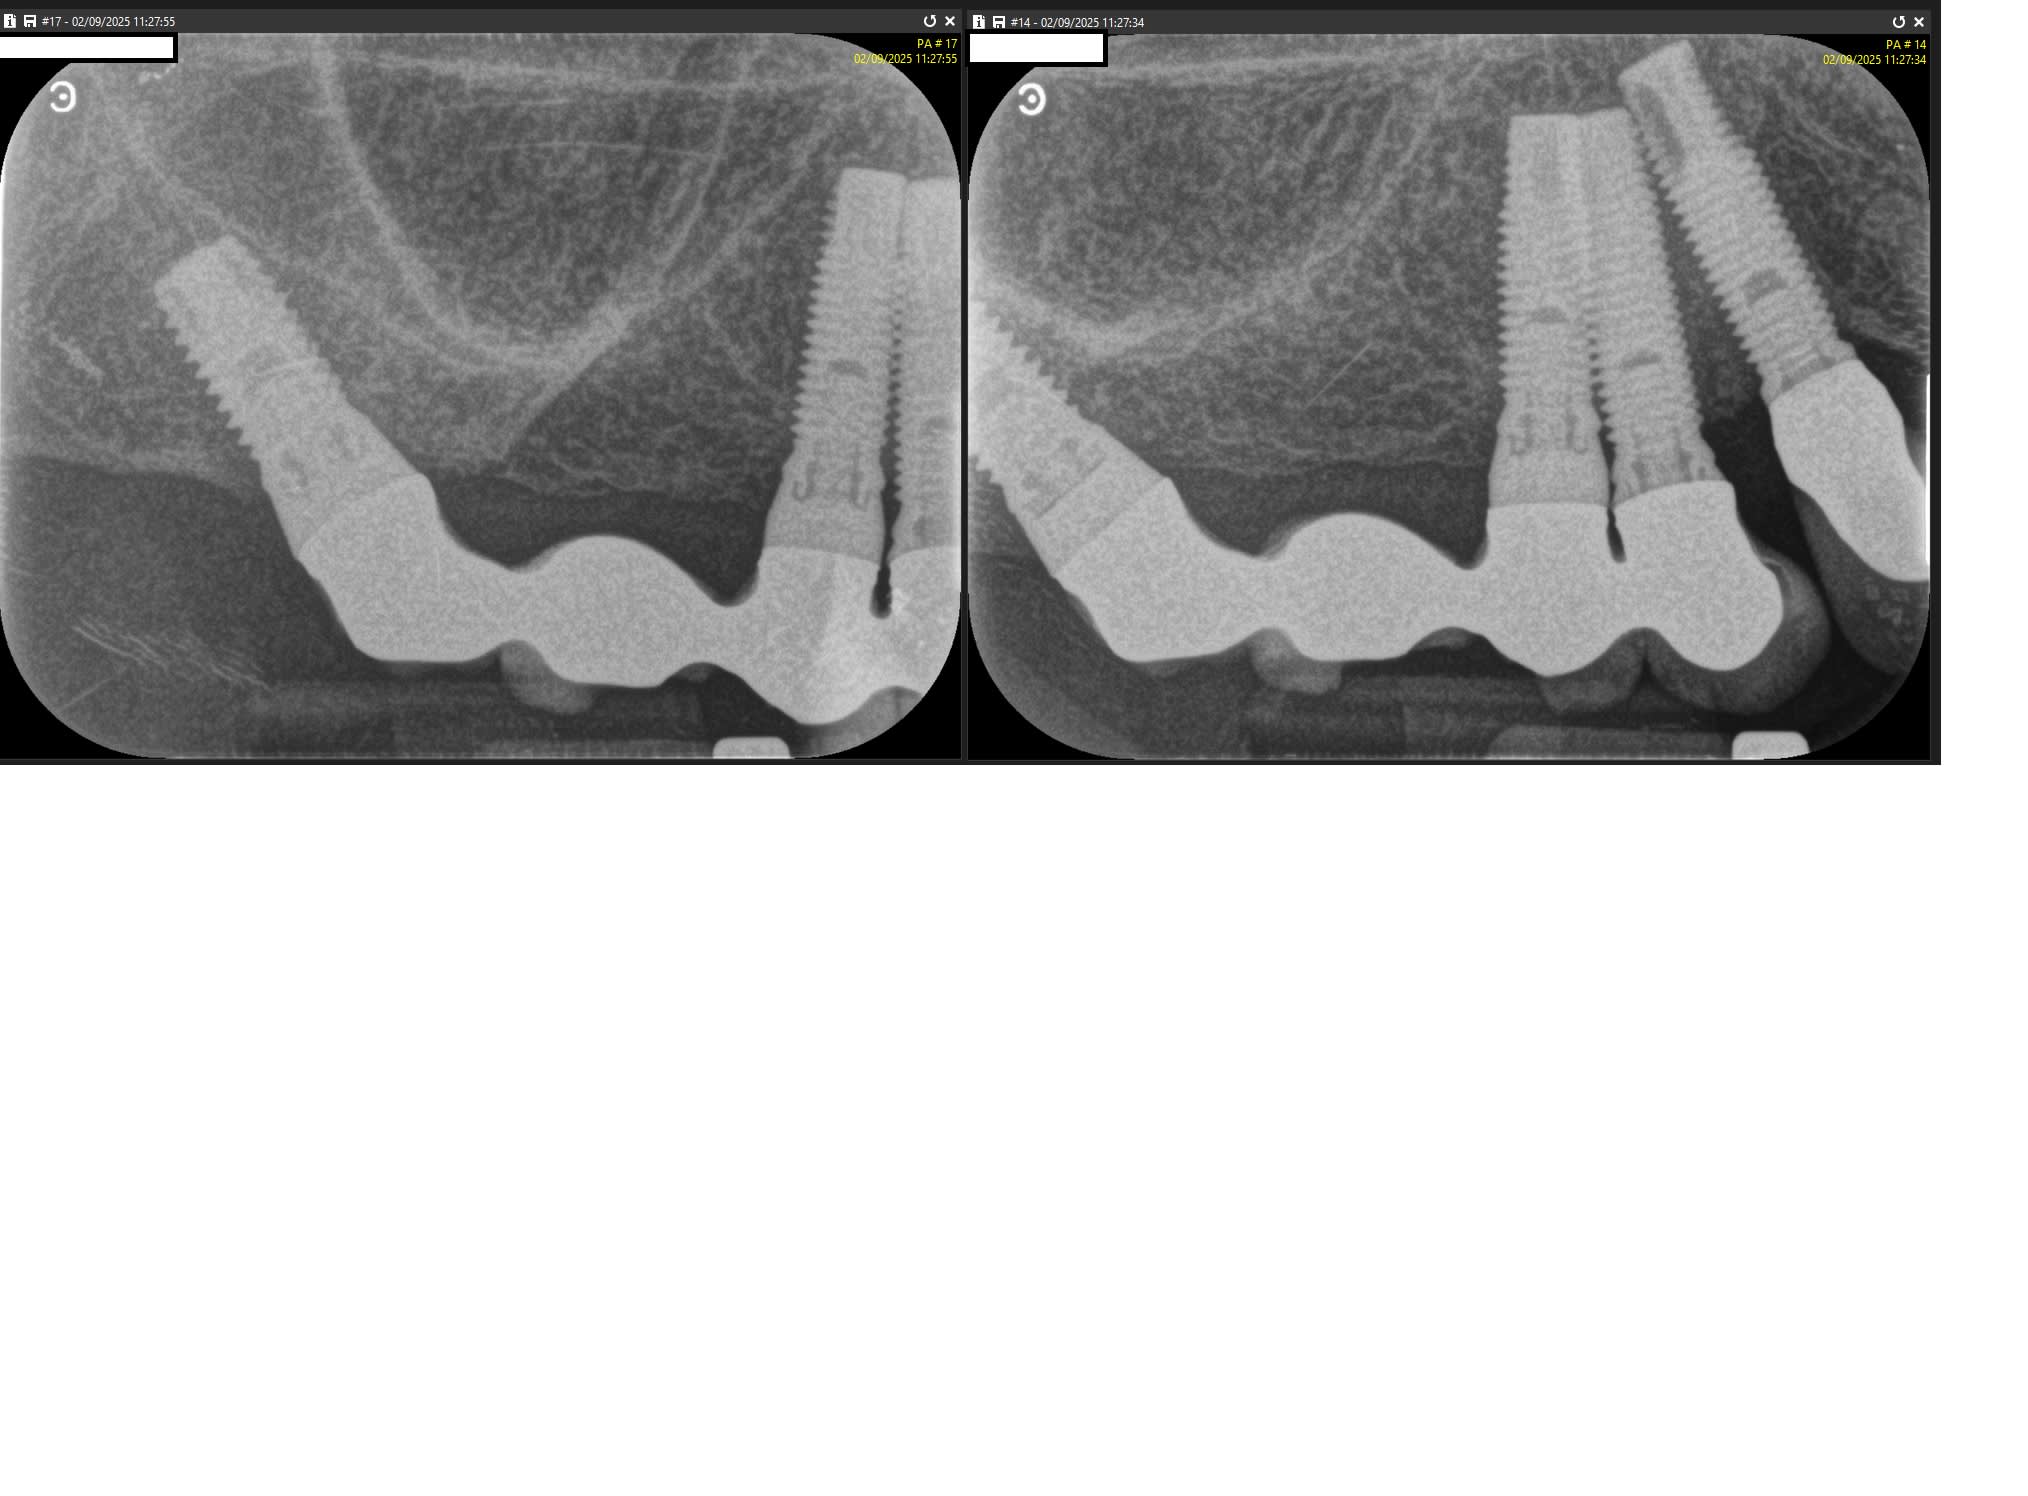

Question récurrente mais pouvez vous me donner votre idée sur la référence de ces implants posés il y a 30 ans.

Je pense qu'ils sont avec une connectique externe donc si je refais le bridge, pas besoin de pilier MUA on est bien d'accord ?

Bonne gueule de Nobel Branemark mk2

https://www.spotimplant.com/fr/implants-dentaire/nobel-biocare/branemark-system-mk-ii-wide

oui, hex externe donc pas de multiunits